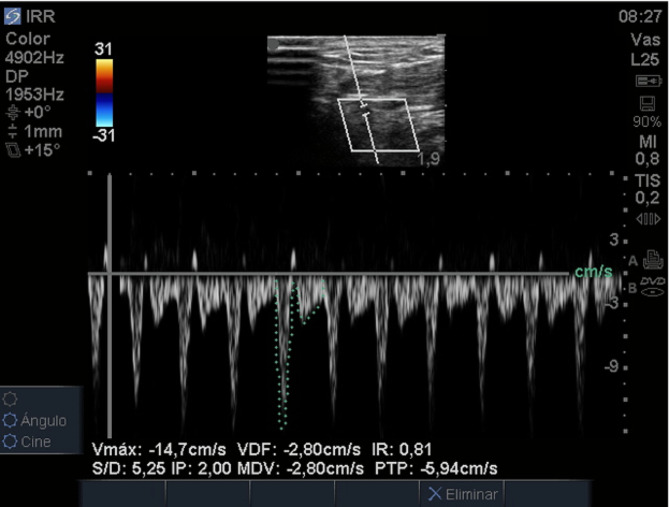

Methods: A cross-sectional study included all consecutive patients undergoing postoperative (POP) cardiac surgery with hemodynamic monitoring using PAC. Hemodynamic assessment was performed using PAC, and RRI was measured with ultrasound in the anatomical snuffbox. The Pearson correlation test was used to establish the correlation between RRI and SVRI measured using PAC. Hemodynamic behavior concerning RRI with a cutoff point of 1.1 (described to estimate under SVRI) was examined. Additionally, consistency between two evaluators was assessed for RRI using the intraclass correlation coefficient and Bland-Altman analysis.

Results: A total of 35 measurements were obtained. The average cardiac index (CI) was 2.73 ± 0.64 L/min/m², and the average SVRI was 1967.47 ± 478.33 dyn·s·m²/cm5. The correlation between RRI and SVRI measured using PAC was 0.37 [95% CI 0.045-0.62]. The average RRI was 0.94 ± 0.11. RRI measurements > 1.1 had a mean SVRI of 2120.79 ± 673.48 dyn·s·m²/cm5, while RRI measurements ≤ 1.1 had a mean SVRI of 1953.1 ± 468.17 dyn·s·m²/cm5 (p = 0.62). The consistency between evaluators showed an intraclass correlation coefficient of 0.88 [95% CI 0.78-0.93], and Bland-Altman analysis illustrated adequate agreement of RRI evaluators.